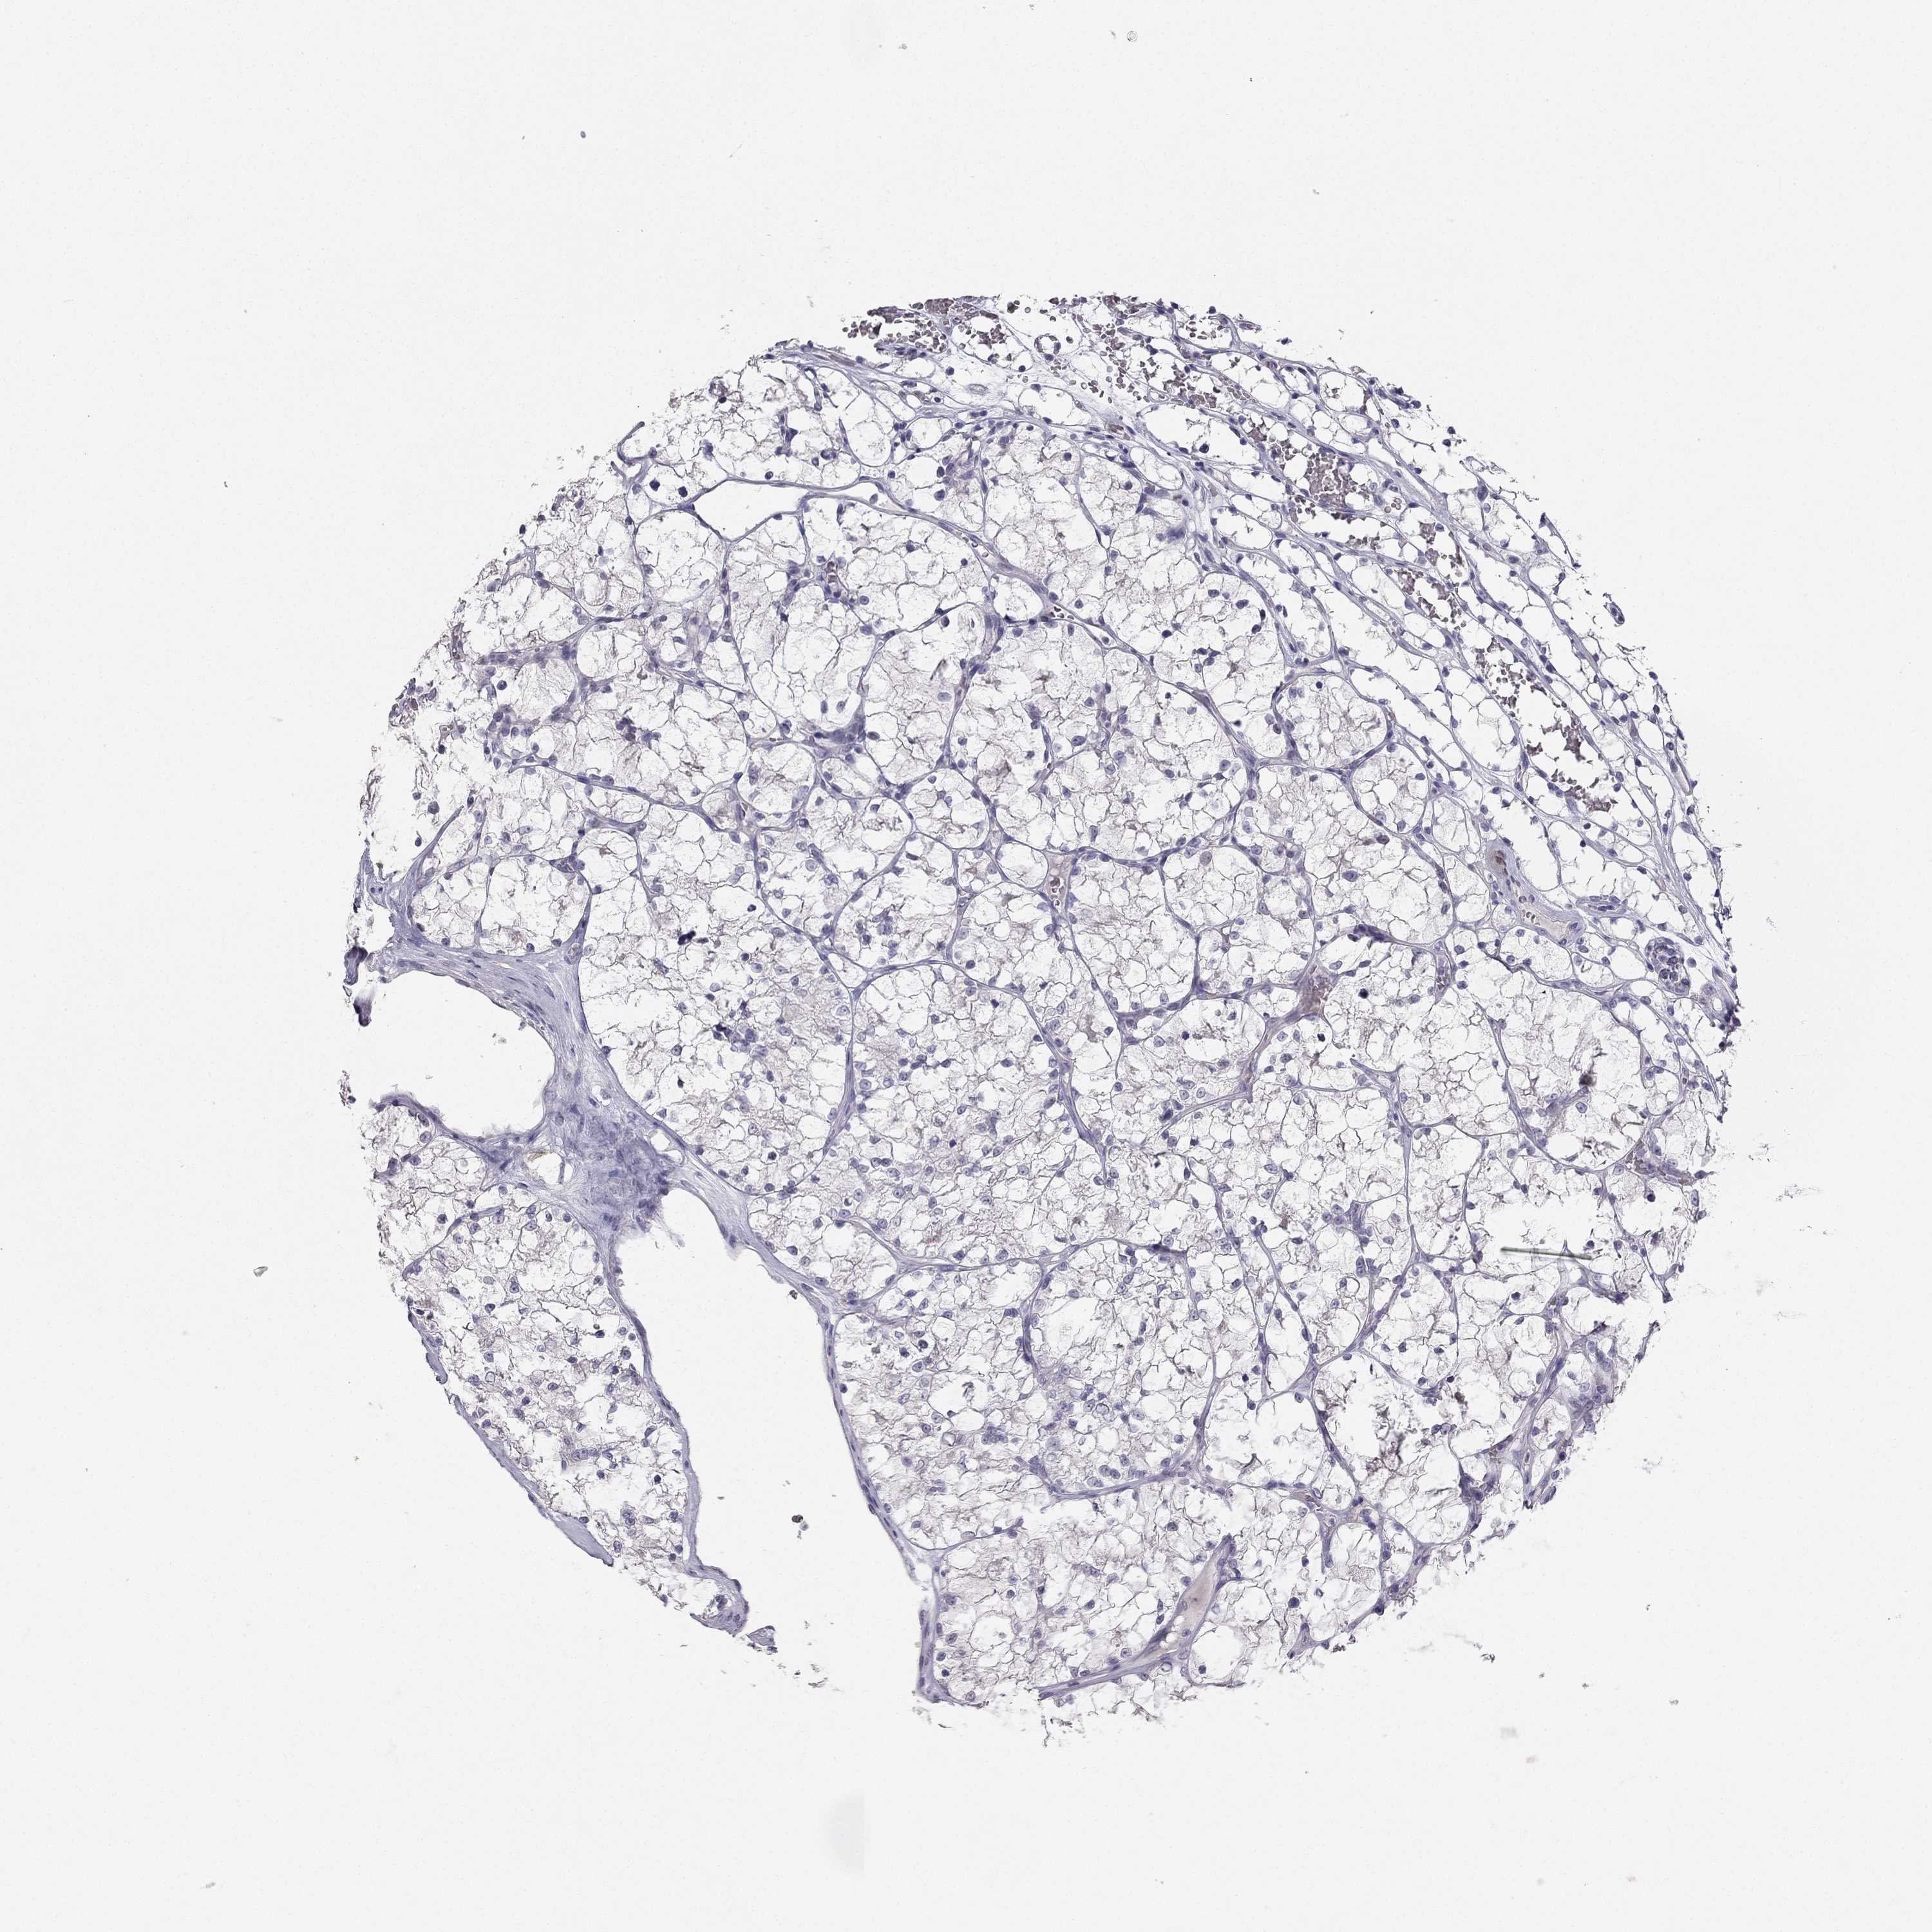

Average pTPM 0.3

Number of samples 521